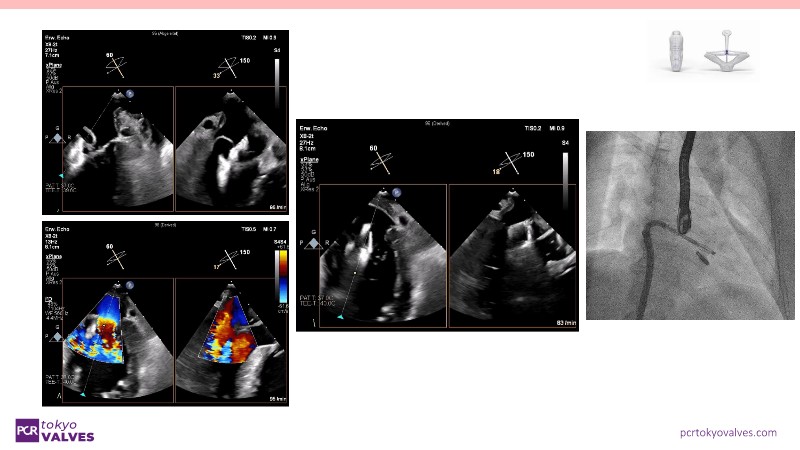

Through case reviews, explore the latest advancements in transcatheter edge-to-edge repair (TEER) for degenerative mitral regurgitation. Discover how a novel TEER device expands treatment possibilities, offering predictable and durable results.